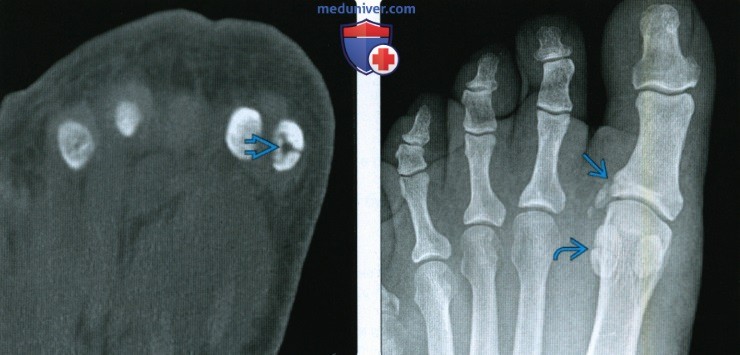

Анатомия: Блоки и сесамовидные кости в деталях